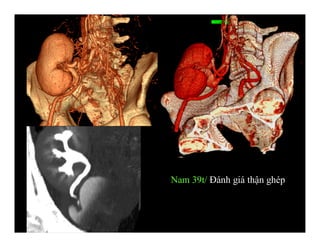

Phình động mạch chủ

bụng

Nam 39t/ Đánh giá thận ghép

Thận ghép